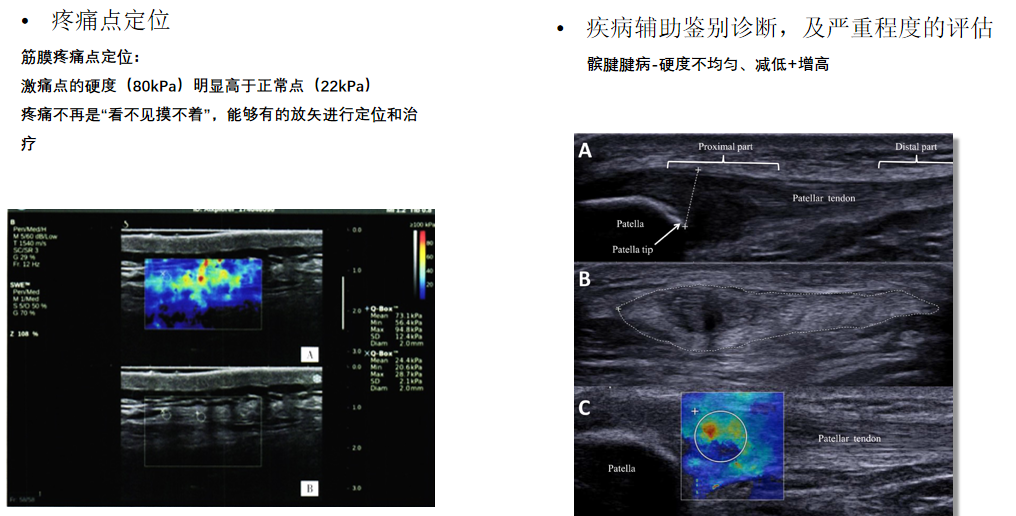

RTE实时弹性成像

?肌骨系统组织的硬度可反应炎症的严重程度?肌肉肌腱组织进行弹性测定,有助于检测创伤性及退变性病变?肌肉肌腱炎性程度评估?精准定位肌痛点?治疗前后功能疗效评估

RTSWE实时剪切波弹性成像

?探头发射激励脉冲进行多点动态聚焦,利用马赫圆锥原理,形成大量的剪切波信号?颜色的变化与剪切波的速度相关,可直接体现肌肉肌腱等组织硬度值?实时、全幅、全定量

鉴别诊断、精准分级、定量评价、穿刺引导、疗效评估、随访观察